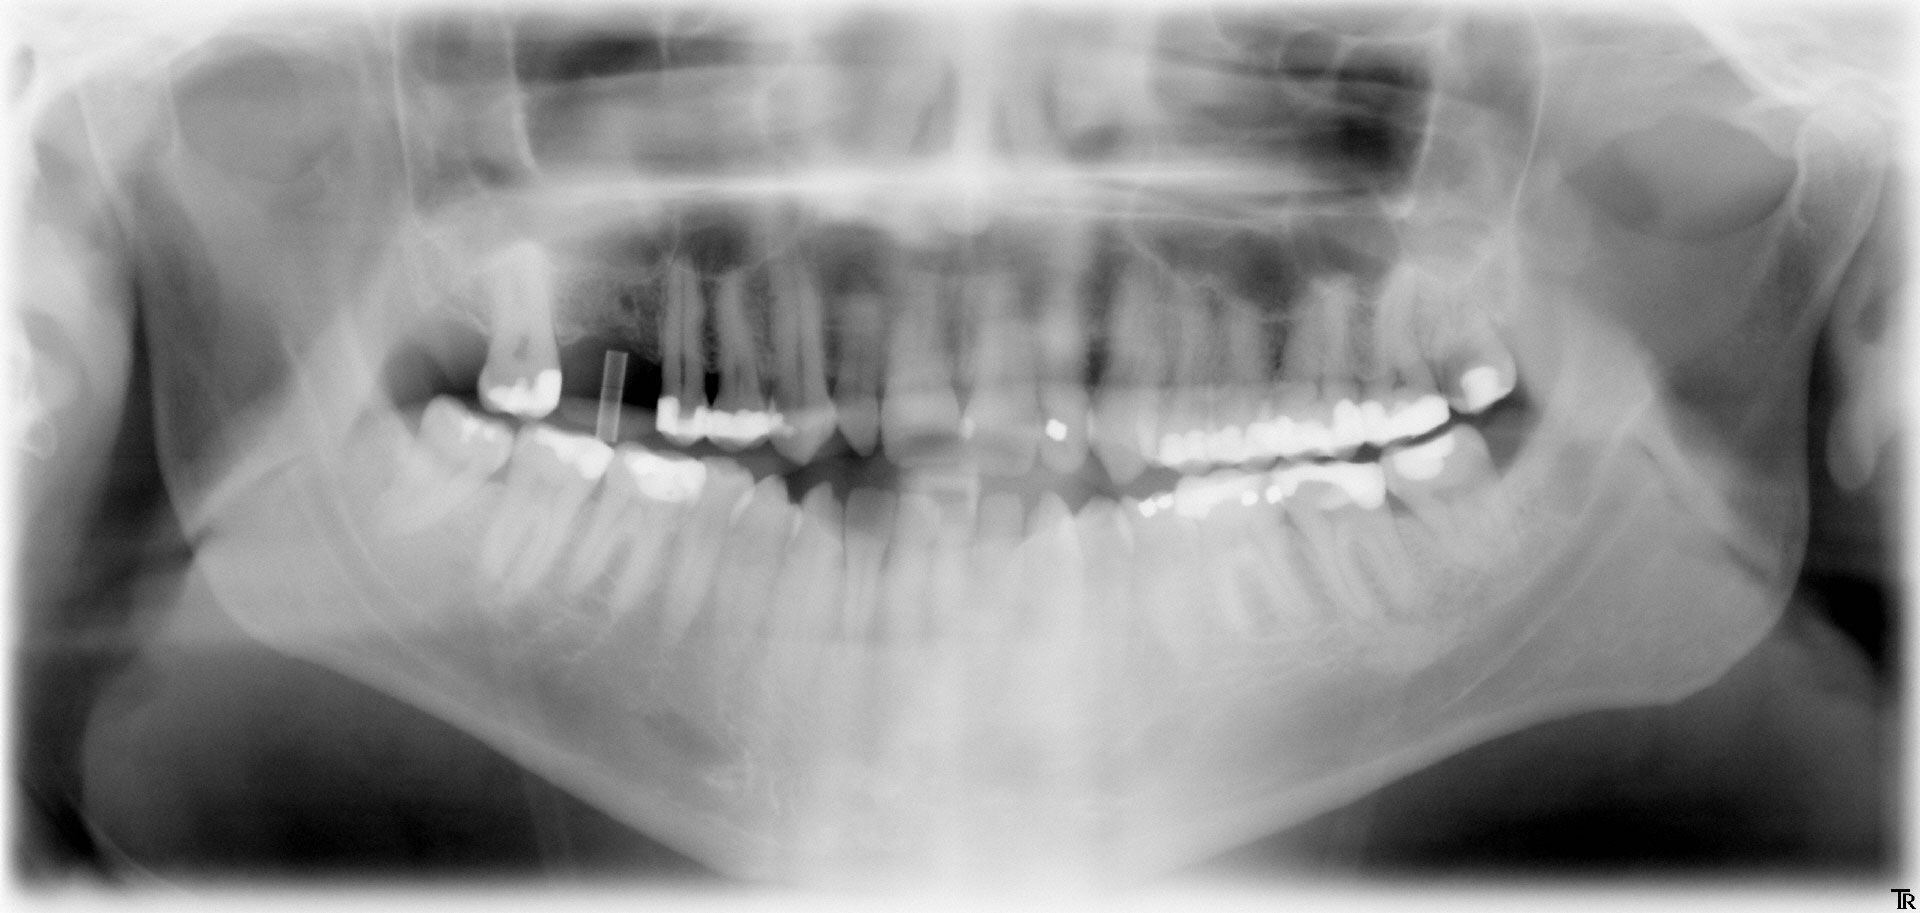

Für ein Implantat werden sowohl eine Mindest-Knochentiefe als auch ein Sicherheitsabstand im Unterkiefer zum Nervenkanal vorausgesetzt. Die Knochentiefe wird durch spezielle Röntgendiagnostik ermittelt.

Panorama-Röntgenaufnahme

Die reale Knochenhöhe wird mit Hilfe einer Tiefziehschiene mit eingearbeiteten Metallkugeln ermittelt. Bei digitalen Röntgengeräten kann gegebenenfalls auf die Messaufnahmen verzichtet werden, da sie über ein integriertes Messtool verfügen. Zur Detailabklärung kann es erforderlich sein, zusätzliche Aufnahmen von einzelnen Zahnabschnitten zu machen.

Durch die Computertomographie kann die Lage der später zu setzenden Implantate im Vorfeld schon auf den Millimeter bestimmt werden.